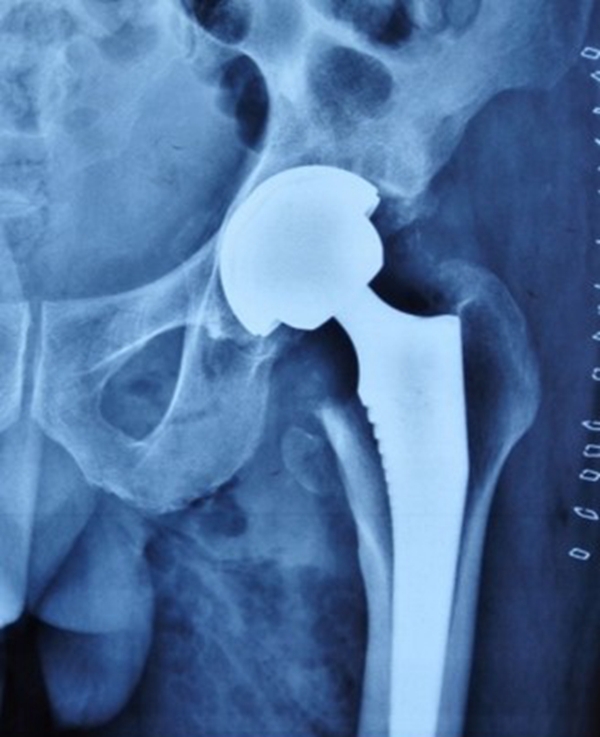

全髋关节置换术具有优异的疼痛缓解、稳定可靠的固定及良好的功能恢复和长期随访结果等优点,常用于治疗各种晚期髋关节疾病。在全髋关节置换中,畸形常发生在股骨侧,非常难处理,是髋关节置换中难题之一。

手术的核心思想:恢复旋转中心、恢复下肢长度、恢复肌肉张力。

髋关节生物力学中,外展肌作用力尤为重要。故外展肌止点位置——大粗隆是术中需要调整的位置。

股骨假体扭力会在健侧肢体离地或着地(如上下楼梯)时达到最大,故生物型假体早期失败在股骨侧常见,而非髋臼侧。

2、假体选择

①保留畸形:表面髋置换、短柄假体。

②让骨骼适应假体:股骨截骨。

③让假体适应畸形:组配式假体

④hybrid、水泥柄。